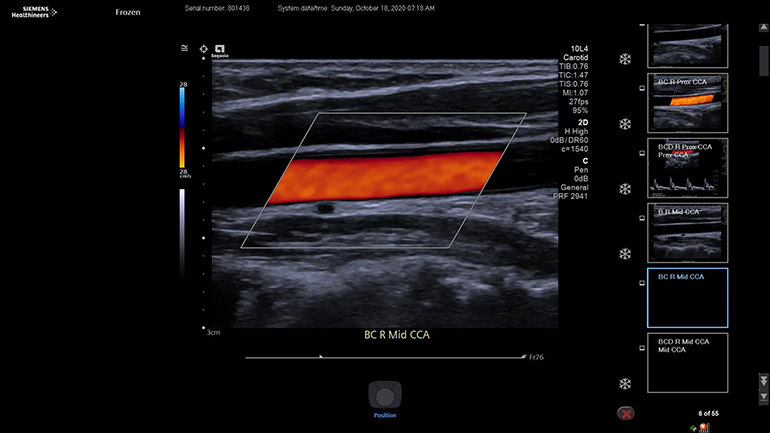

Технологии цветовой визуализации

Подавление артефактов яркости цвета

В системе ACUSON Sequoia реализована технология коррекции скорости звука, которая изменяет скорость ультразвуковых волн в зависимости от типа ткани или патологии и тем самым позволяет улучшить фокусировку, пространственное и контрастное разрешение изображений.

Технология улучшенного отображения просвета сосудов Clarify Vascular Enhancement

Технология Clarify Vascular Enhancement позволяет уменьшить количество артефактов, часто встречающихся на изображениях просвета сосудов и камер сердца плода, улучшает дифференцировку границ сосудов, позволяет значительно повысить качество визуализации сосудов малого диаметра.

Технология Slow Flow State

В технологии Slow Flow используются интеллектуальные фильтры, которые позволяют выделить кровеносные сосуды с помощью фильтрации движения, адаптивно улучшают ЭХО- сигнал и подавляют артефакты яркости. Эти интеллектуальные фильтры могут обнаруживать и маркировать низкоскоростной кровоток, который в противном случае был бы смешан с шумовыми артефактами и исключен из визуализации из-за скоростных ограничений, применяемых в обычном допплеровском режиме.

Технология Dynamic MultiHertz

Интеллектуальный инструмент автоматизации исследования, который автоматически регулирует частоту сканирования в В-режиме и в цветовом режиме в соответствии с положением окна цветового изображения.